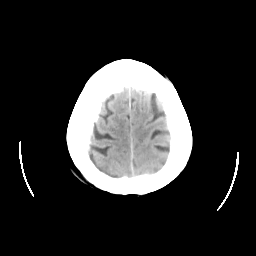

CT Study #2 -- Slice #25